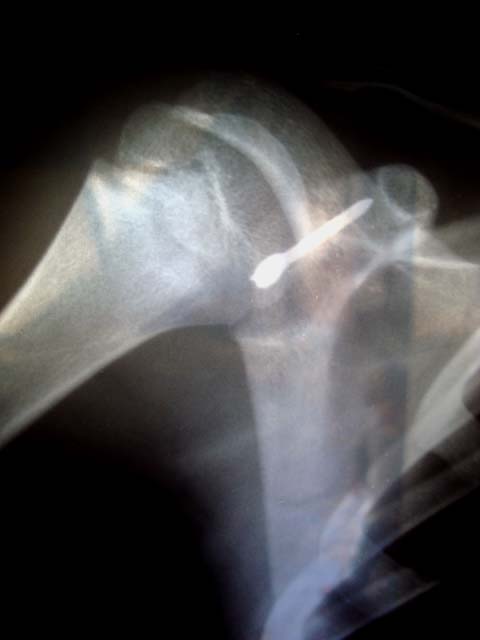

Although Abu Jerrad’s father Khalil had been inside the doorway, he too was hit by the darts. Abu Jerrad’s son Khalil was hit by darts in his right foot and in one finger. One of the flechettes that struck Abu Jerrad remains deeply embedded near his spinal cord. Doctors fear removing the dart would injure a nerve and leave Abu Jerrad paralyzed.

According to Dr. Bakkar, in Gaza it won’t be possible for Abu Jerrad to get the surgery he needs. “We don’t have qualified specialists to do such intricate surgery in Gaza. He’d need surgery outside.” With more than 280 patients dead after being prevented by Israel, which controls Gaza’s borders, from reaching medical treatment outside of Gaza, Abu Jerrad holds no prospect of being granted permission by Israeli authorities to leave Gaza for surgery.

The two-inch-long scar on Rami al-Lohoh’s right shoulder is his reminder of the painful dart which had penetrated deeply beneath the flesh of his shoulder area. The 11-year-old was too shy to speak of his injury, but obligingly pulled his shirt aside to reveal the scar. X-rays taken after the dart had embedded in al-Lohoh reveal the depth of its penetration.

“The doctors were afraid of this type of injury, so they hesitated before doing the operation to remove the dart,” Rami’s father Darwish al-Lohoh explained. After a 2.5 hour operation, the potentially deadly dart was removed.

*x-ray of Mohammed Abu Jerrad’s spine and the dart dangerously close to it Photos | Eva Bartlett